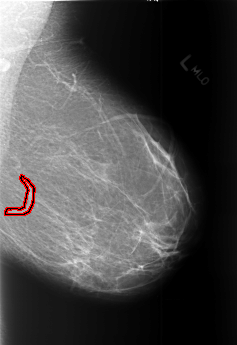

FILE: B_3453_1.LEFT_MLO.OVERLAY

TOTAL_ABNORMALITIES 1

ABNORMALITY 1

LESION_TYPE MASS SHAPE TUBULAR MARGINS N/A

ASSESSMENT 2

SUBTLETY 3

PATHOLOGY BENIGN_WITHOUT_CALLBACK

TOTAL_OUTLINES 1

BOUNDARY

FILE: B_3453_1.LEFT_CC.OVERLAY